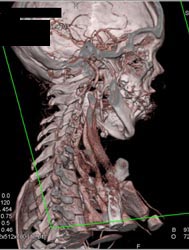

Carotid Artery Ectasia